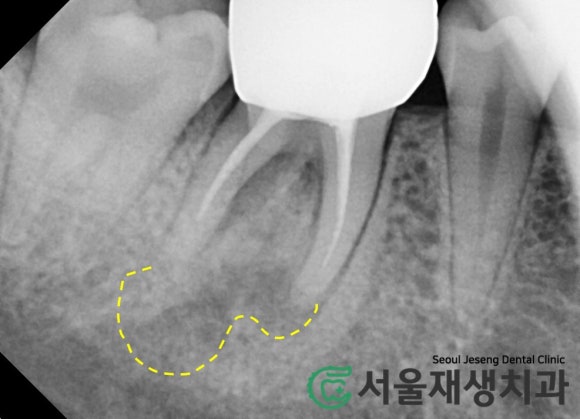

치아 뿌리 끝을 감싸는 동글동글하고

까만 빈 공간이 보이시나요?

바로 치근단염증입니다.

치근단염증(=뿌리염증)이란?

치아 뿌리 내에서 부패한 신경 조직들이

뿌리 끝의 조그마한 구멍을 통해 배출되어

뼈를 삭게 만드는 현상입니다.

치근단염증치료에 대한 경험이 부족하면

조금만 큰 치근단염증을 보더라도

급히 발치를 결정하게 될 수 있습니다.

대부분의 치과의사에게

다가가기 힘든 고난이도의 치료이기

때문이지요.